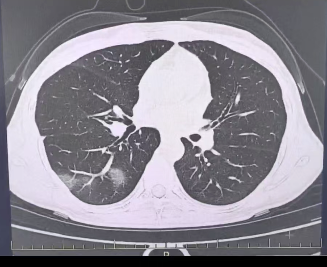

肺炎图片来源于稿源单位

结果情况反而进一步加重:好几叶肺都出现了“白肺”现象,指间血氧饱和度只有88%,血心肌酶谱、肌钙蛋白的指标、肝功能的指标也出现了明显的异常。

肺炎图片来源于稿源单位

所以,肺炎也是流感最常见的并发症之一,可引发包括原发流感病毒性肺炎、继发细菌性肺炎、细菌和病毒混合感染性肺炎,会有高热、咳嗽、咳痰、呼吸困难等症状,严重时可出现呼吸衰竭。